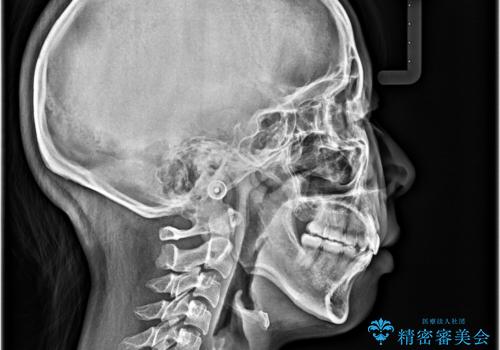

上下の前歯が接触する仕上がりとなったので、横顔の印象が大幅に改善されました。